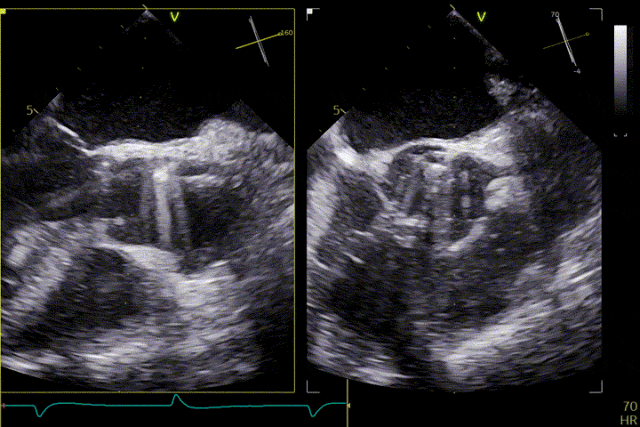

在超聲引導下,手術團隊高效且精準地完成了瓣膜的定位、釋放及功能評估。手術過程順利,夾持件入竇與定位一氣呵成,三枚夾持件的釋放與錨定位置均與術前評估完全一致,器械操作時間約5分鐘。術中超聲評估顯示無瓣周漏,血流動力學表現穩定,手術順利完成。

患者主動脈瓣重度反流得到糾正,術後無反流、無瓣周漏。術後心臟超聲顯示人工生物瓣啟閉功能良好,平均跨瓣壓差2 mmHg,血流速度正常。患者恢復情況良好,心功能較術前明顯改善。